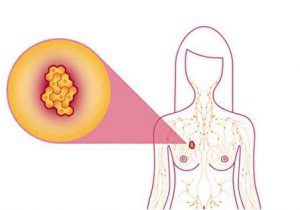

علائم سرطان سینه و نشانه های اولیه آن چیست؟

سرطان سینه یا پستان چیست؟ (علت، علائم، راههای درمان آن)

علت سرطان سینه چیست؟

علائم سرطان سینه چیست؟